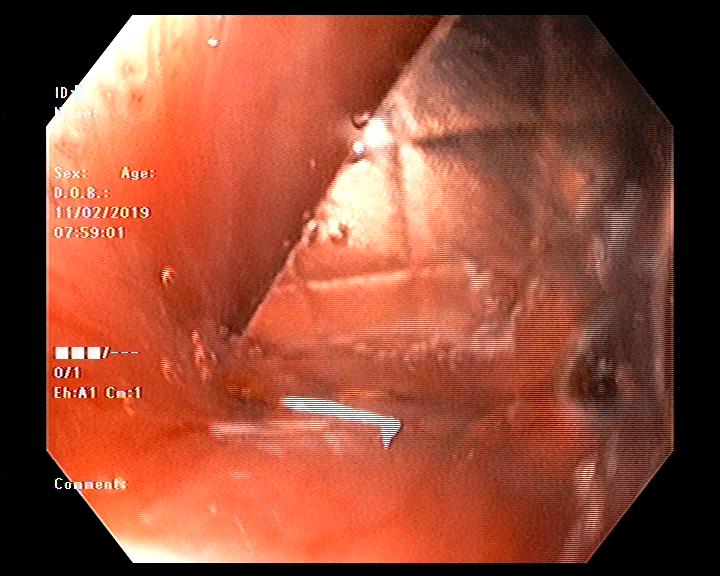

Nội soi phát hiện vỉ thuốc cắm vào thành thực quản

Bác sỹ Nguyễn Thị Cúc - Phó Khoa Chẩn đoán hình ảnh, phụ trách bộ phận nội soi cho biết: Sau khi hội chẩn, Ê kíp đã tiến hành nội soi gây mê thực quản bằng ống mềm để gắp dị vật. Chỉ sau 20 phút, dị vật là một vỉ thuốc còn nguyên vỏ với các cạnh sắc nhọn, cắm vào thành thực quản, đường kính khoảng 2 x 2,5cm đã được gắp ra. Sau thủ thuật, bệnh nhân hết nuốt vướng, không ho khạc ra máu và được xuất viện cùng ngày.

Vỉ thuốc được gắp ra có kích thước khoảng 2 x 2,5cm